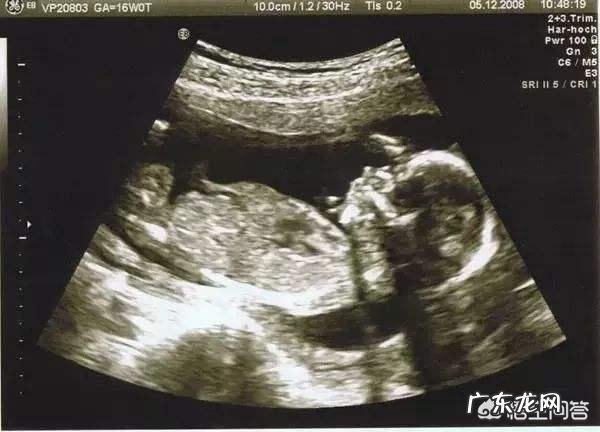

讲了宝妈,再来讲讲宝宝,孕4个月时宝宝身长约16cm,体重约110克 。B超下生长发育情况如下图: